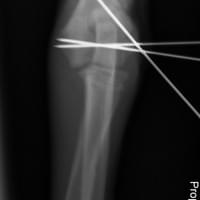

Chirurgia ortopedica

Nella nostra struttura si offre un servizio di chirurgia ortopedica tramite l’utilizzo di diverse tecniche operatorie, quali i fissatori esterni e l’utilizzo di placche e viti (fissazione interna), per il trattamento delle fratture .Per il trattamento della Rottura del legamento crociato craniale del ginocchio, si effettuano le metodiche piu’ moderne come: la TTA POROSA (tibial tuberosity advancement) e la TPLO (osteotomia livellante del piatto tibiale) .

Ci occupiamo anche delle patologie chirurgiche legate alla Displasia di rotula.